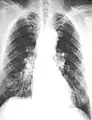

The abnormal chest x-ray and its interpretation remain the most important factors in establishing the presence of pulmonary fibrosis.[11] The findings usually appear as small, irregular parenchymal opacities, primarily in the lung bases. Using the ILO Classification system, "s", "t", and/or "u" opacities predominate. CT or high-resolution CT (HRCT) are more sensitive than plain radiography at detecting pulmonary fibrosis (as well as any underlying pleural changes). More than 50% of people affected with asbestosis develop plaques in the parietal pleura, the space between the chest wall and lungs. Once apparent, the radiographic findings in asbestosis may slowly progress or remain static, even in the absence of further asbestos exposure.[25] Rapid progression suggests an alternative diagnosis.

Severe pleural fibrosis with focal calcification